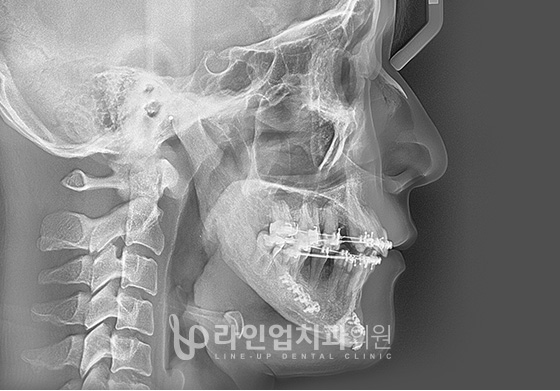

ЭТАПЫ ОПЕРАЦИИ

01

Резекция челюсти с задней стороны моляров до височно-нижнечелюстного сустава

02

В зависимости от плана операции челюсть перемещается в нужное положение

03

Фиксируется специальными пластинами

ФОТО ДО И ПОСЛЕ

Before

After